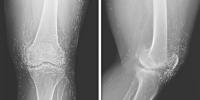

جوڑوں کے درد میں مبتلا خاتون کے گھٹنوں میں سونے کے دھاگوں کی موجودگی کا انکشاف